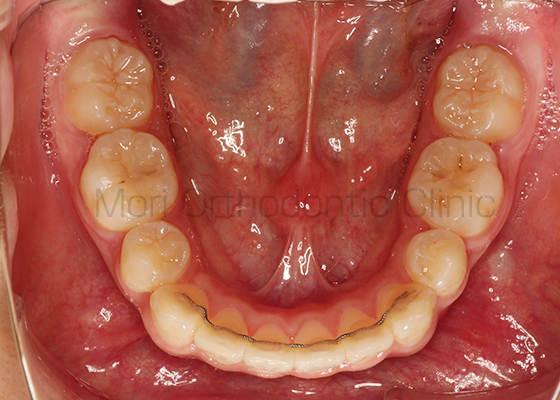

術前

術後

| 主訴 | 歯並び、八重歯 |

|---|---|

| 診断名 | AngleⅡ級叢生 |

| 年齢 | 30歳2か月 |

| 治療装置 | Multi-Bracket(表側矯正)、CARRIERE DISTALIZER |

| 抜歯部位 | 14,24,35,45 |

| 治療期間 | 2年1か月 |

| 治療費 | 825,120円(税込) |

| リスク・副作用 | 矯正治療による歯の移動に伴う痛み、歯根吸収、歯肉退縮、虫歯 |